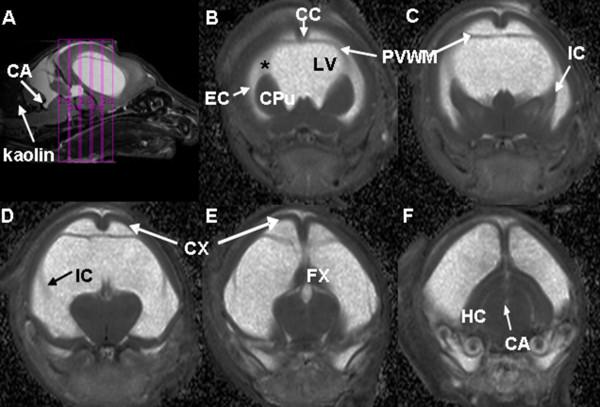

DTI data were acquired between postnatal day 7 (P7) and P12 in 12 rats with HCP induced at P2 and in 15 age-matched controls. Animals were euthanized at P11 or P22/P23 and brains were processed with immunohistochemistry for glial fibrillary acidic protein (GFAP), ionized calcium-binding adaptor molecule (Iba-1), and luxol fast blue (LFB) to assess astrocytosis, microglial reactivity and degree of myelination, respectively.

Hydrocephalic rats were consistently found to have an abnormally low (at corrected p-level of <0.05) fractional anisotropy (FA) value and an abnormally high mean diffusivity (MD) value in the cerebral cortex (CX), the corpus callosum (CC), and the internal capsule (IC). Immunohistochemical analysis demonstrated trends of increasing astrocyte and microglial reactivity in HCP rats at P11 that reached statistical significance at P22/P23. A trend toward reduced myelination in the HCP rats was also found at P22/P23. Correlation analysis at P11 for the CC demonstrated statistically significant correlations (or trends) between the DTI measurement (the decreased FA and increased MD values) and the GFAP or Iba-1 rankings. The immunohistochemical rankings in the IC at P22/P23 were also significantly correlated or demonstrated a trend with both FA and MD values.